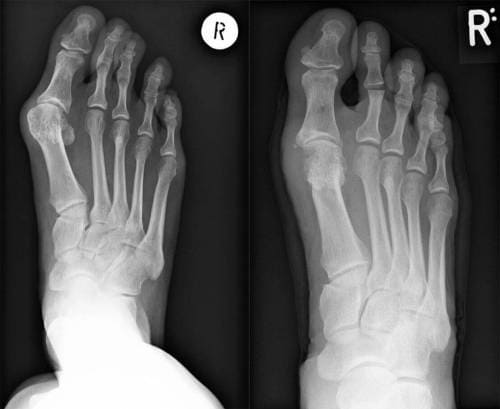

Raze X ale picioarelor înainte și după tratament

Operație pentru îndepărtarea osului din picior. După ce a făcut o radiografie, chirurgul a concluzionat tragic că este nevoie urgentă de o intervenție chirurgicală pentru îndepărtarea degetului strâmb. Degetul răsucit provocase deja complicații la articulațiile piciorului, din cauza căreia unele dintre ligamentele din interiorul piciorului au fost lezate, în curând ar începe necroza și, prin urmare, piciorul ar trebui amputat.